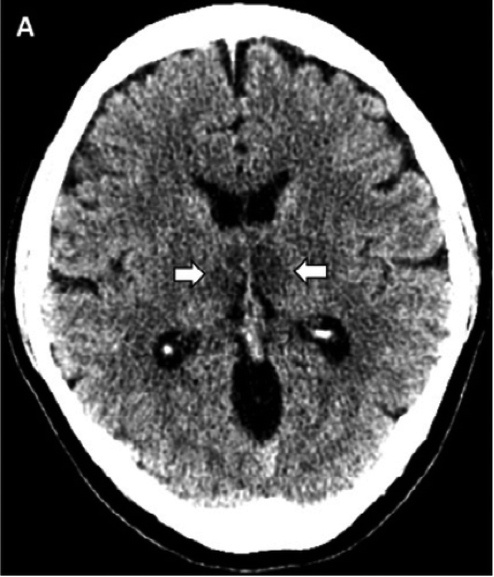

Ей провели компьютерную томографию без контраста, КТ-ангио- и венографию (с введением контрастного вещества), а также магнитно-резонансную томографию с контрастированием. Со стороны сосудов головного мозга никаких изменений не наблюдалось, чего нельзя было сказать про мозговое вещество.

КТ головного мозга пациентки. Стрелочками показаны поражения таламусов (гиподенсные зоны). Credit: Brent Griffith et al. / Radiology 2020

И на КТ, и на МРТ было выявлено симметричное поражение таламусов, на МРТ также обнаружили поражение медиальных отделов височных долей и субостровковых областей. При введении контрастного вещества наблюдалось его кольцевидное накопление, что говорило о нарушении в местах поражения мозговой ткани гемато-энцефалического берьера. Причем, в этих же местах обнаруживались мелкие кровоизлияния.